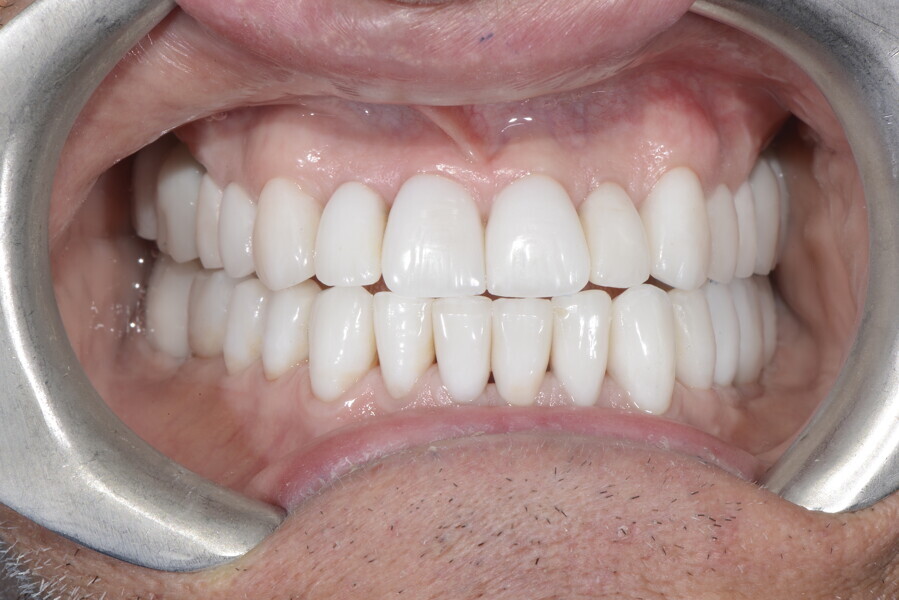

After the first phase of aligner treatment, we had achieved better inter-arch coherence, better maxillary arch expansion, and some space for improving the anterior tooth proportions restoratively (Fig. 19). We then temporarily restored the anterior teeth directly with composite, closing the spaces, improving the tooth proportions and further increasing the maxillary arch expansion (Fig. 20). We used restorative arch expansion to reduce the orthodontic destabilisation of the teeth to achieve the correct inter-arch coherence and retain the teeth in the cortical bone.38 A refinement aligner phase was undertaken to improve the final alignment of the gingival zenith and to improve the inter-arch coherence (Fig. 21). The periods of the first orthodontic phase and of the refinement were used to augment the mandibular and maxillary bone and to place the implants (Fig. 22). At the end of the orthodontic treatment, the case was finalised with ceramic veneers in the anterior area and temporary restorations on the implants in the posterior area (Figs. 23–26).

The provisional phase of about four months was important to allow the peri-implant tissue to mature and to teach the patient to chew correctly with chewing gum, cotton rolls and silicone masticatory sticks. This is fundamental training for the patient to achieve the correct alternating unilateral masticatory cycle needed to obtain the ideal rehabilitation of the masticatory system. We wanted the patient to achieve ideal masticatory and swallowing function. After sufficient rehabilitation time, we finalised the case with posterior zirconia crowns screwed on to the implants (Fig. 27).26

Our ideal final rehabilitation goals were:

• posterior stability;

• inter-arch coherence and U-shaped arches;

• anterior freedom during mastication;

• minimum disclusion vertical dimension;

• alternating unilateral masticatory cycle;

• physiological swallowing and high tongue posture against the palate; and

• mandibular disclusion advancing the mandible freely.

For maintenance purposes, after prosthetic finalisation, the patient was to carry on with the Froggymouth therapy and to use the Ri.P.A.Ra. for physiotherapeutic exercises and mastication training (Fig. 28). It was strongly recommended that the patient wear a mandibular occlusal splint during sleep. This occlusal splint was designed with disclusion guides to advance the mandible and ensure balanced contralateral support (Fig. 29).11, 39 We achieved an aesthetic appearance with adequate inter-arch coherence and a better cephalometric result (Figs. 30 & 31).